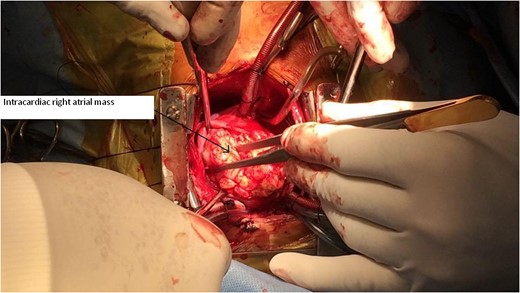

A 2-year-old male child was brought to hospital with respiratory distress since last 2 weeks. He was having repeated respiratory tract infection since last 3 months along with poor oral intake and poor activity. His symptoms progressed from New York Heart Association (NYHA) Functional Class II to IV over last 2 weeks. On investigation at another hospital he was diagnosed with intracardiac mass having extracardiac extension. Parents brought the child to our hospital for further management.

CT Thorax showing intracardiac right atrial mass with extracardiac extension.

Our case report is unique, in that intracardiac tumour had extracardiac extension by infiltration through right atrial wall. Previous four reports mention purely intracardiac mass. The rarity in the literature of such pathological occurrence makes our case report very unique.